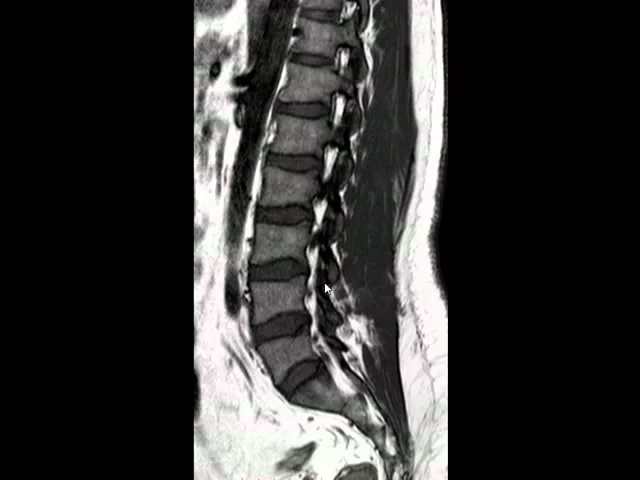

inferior ao músculo piriforme músculo piriforme tá aqui nervo ciático sai indo aqui músculo piriforme nervo ciático Então essas são as principais estruturas que vemos aqui no plano coronal aqui no plano sagital sequência ponderada em 2 T2 porque o líquido está Branco está brilhando tem hipersinal então a água branca é T2 nós temos aqui a medula espinhal com a Calde equina e aqui o Lor né o espaço raquidiano e as raízes da Calde equina aqui é a duram Mater esse traço escuro a duram Mater que forma saco dural veja que Aqui termina o saco dural e

aqui eu filo um terminal e atrás dela é a gordura epidural então aqui é gordura epidural esse branquinho é a gordura epidural a faixa escura é a dura Mater e esse branco aqui atrás é a gordura epidural então dura Mater gordura epidural a gordura tem hipersinal no T2 Veja aqui a gordura no tecido subcutâneo semelhante ao líquor aqui a Calde Quina as raízes da Calde equina aqui os processos espinhosos os processos espinhosos aqui processo espinhoso aqui os ligamentos interespinhosos ligamentos interes e aqui o ligamento supraespinhal ligamento supraespinhal ou supraespinhoso nós temos os corpos vertebrais com

essa morfologia a face anterior ele é sempre côncava os corpos vertebrais o córtex tem ausência de sinal é preto a medula tem um sinal intermediário esse triangulo Zinho branco é gordura ao redor da veia base vertebral a veia base vertebral é união de várias veias que drenam o corpo vertebral e ela sai por aqui para o espaço epidural espinhal a duramáter fica colada aqui e nós temos os discos intervertebrais com o anel fibroso que é essa porção escura e o núcleo pupos o núcleo pupos é é a porção mais branca é mais branco porque ele

tem mais água é mais hidratado e quanto mais água em T2 mais branco fica então anel fibroso núcleo pupos nós temos também o ligamento longitudinal posterior que é colado aqui não não tem como a gente individualizá-la normalmente não conseguimos individualizar o ligamento da do córtex posterior do corpo vertebral e do anel fibroso em condições normais não conseguimos individualizá-la no T2 e anteriormente também tem um ligamento longitudinal anterior da mesma forma a gente não consegue individualizá-la em condições normais aqui o sacro n S1 L5 L4 L3 L2 L1 T12 veja que o cone medular aqui terminou

em T12 e no mais lateralmente veja as raízes da Calde Quina as raízes da Calde Quina e Aqui começa a aparecer os forames intervertebrais veja forame intervertebral forame intervertebral forame intervertebral veja os forames intervertebrais que fica entre os pedículos aqui é um pedículo aqui é outro pedículo entre eles fica o forame vertebral essa bolinha é o gango da raiz nervosa a raiz nervosa sai por aqui ela tem um gang forma essa bolinha e esse essas outras bolinhas aqui são vasos radiculares artéria e veias radiculares que entram e saem junto com a raiz nervosa e o

branco ao redor é gordura epidural gordura que sai envolvendo a bainha da nervosa aqui o disco intervertebral veja que a raiz nervosa sai na porção mais superior do Fame e o disco está na porção mais inferior mas o forame está preservado neste caso aqui normal Aqui nós temos um pedículo processo articular superior pars interarticulares ou Timo e processo articular inferior Veja aqui a raiz SA vasos o forame aqui a mesma coisa veja aqui na frente a horta e aqui a veia cava inferior Então essas são as principais estruturas normais que nós vemos na ressonância magnética

da coluna lombar no corte sagital T2 aqui temos o corte sagital T1 veja que o licor é escuro a água Escura em T1 Aqui está a medula espinhal cone medular a Calde Quina veja que a gordura epidural é branca ess essa parte branca a gordura epidural espinhal semelhante a gordura do subcutâneo como o licor é escuro então aqui conseguimos fazer bem a diferenciação entre a gordura epidural e portanto esta linha é dura Mater e o líquor na sequência T1 na sequência T2 as duas coisas eram brancas o corpo vertebral tem um sinal um pouco mais

alto que o disco e os discos intervertebrais esse sinal Cinza o córtex também tem ausência de sinal é preto escuro os forames intervertebrais nós vemos muito bem porque tem gordura rodeando as estruturas que entram e saem do forame aqui as raízes nervosas saindo e pequenos vasos que transitam pelo forame e ao redor gordura circundando as estruturas neurovasculares Aqui nós temos o pedículo processo articular superior processo articular inferior articulação interapofisária veja aqui pedículo processo articular superior e inferior articulação interapofisária articulação interapofisária a ressonância não é o melhor exame para avaliarmos as estruturas ósseas dos elementos posteriores

ela é boa para os corpos vertebrais os discos a medula as raízes neurais todo o compartimento interno ela é muito boa mas para elementos posteriores a gente perde bastante estruturas e aqui atrás é o ligamento Amarelo ligamento Amarelo está aqui aqui a duramater espaço epidural ligamento Amarelo aqui os processos espinhosos ligamentos Inter interespinhosos e ligamento supraespinhoso liga os processos espinhosos aí e aqui a musculatura para vertebral de um lado e do outro esta sequência é um T2 com saturação de gordura veja que o Lor continua branco com hipersinal e portanto é um T2 só que

a gordura ficou escura a gordura fica escura porque saturamos a o sinal então T2 com saturação de gordura veja que a gordura da medula óssea fica escura a gordura do tecido subcutâneo fica escura a gordura intra pélvica e intraabdominal fica escura só que isso ressalta o edema esse paciente tem um discreto edema no tecido subcutâneo aqui dorsal as outras estruturas são semelhantes né o núcleo pupos o anel fibroso quando você satura gordura os vasos brilham Então você veja aqui também as veias base vertebrais entrando nesse espaço triangular sempre aqui posteriormente e aqui vamos fazer a